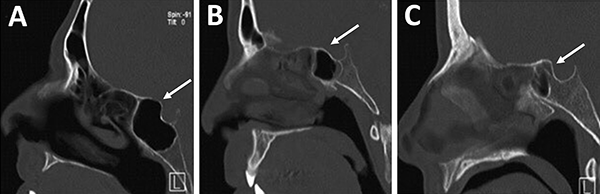

La principal utilización de la tomografía es la identificación de estructuras anatómicas óseas útiles a la hora de la planificación quirúrgica. Con una tomografía con reconstrucción 2D se pueden evidenciar con sencillas mediciones las siguientes características: septum nasal, variantes turbinales, presencia y posición de los ostiums esfenoidales, rostrum esfenoidal y su relación con el vómer, neumatización del seno esfenoidal, tabiques intrasinusales, distancia intercarotídea, grado de neumatización de etmoides posterior e identificación de nervios ópticos en su trayecto adyacente al seno esfenoidal.23,29

Respecto a los ostium esfenoidales, cabe destacar que son el punto de entrada óptimo al seno esfenoidal. En caso de ser dificultosa su localización (situación frecuente) se podría ingresar al seno esfenoidal aproximadamente 1,5 cm por encima del borde superior de la coana (fig. 11).23,13

Figura 11: Ostium esfenoidales identificables en TC. A) TC corte axial; B) TC corte sagital.